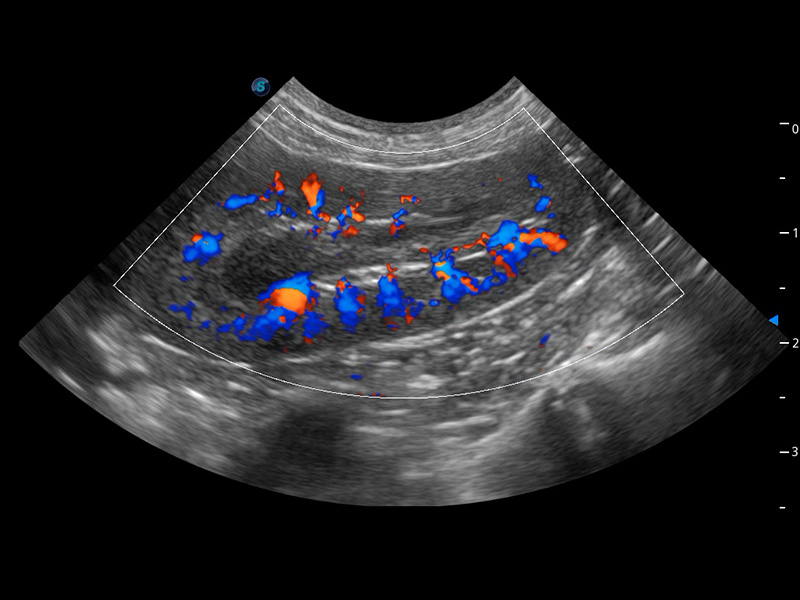

ProPet 60 作为一款高端台式动物超声设备,为动物医生的日常诊断提供了一系列贴合动物临床需求、解决临床实际问题的高级成像功能。凭借全系列高清探头,满足医生对腹部、心脏、生殖、浅表、肌骨等成像的所有需求,切实帮助您提升检查效率,提高诊断信心。

兽用彩色多普勒超声诊断系统